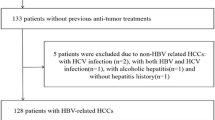

This retrospective study followed the principles of the Declaration of Helsinki and was approved by the Institutional Review Board. Written informed consent was waived. Between 1 March 2014 and 31 July 2017, all patients referred for abdominal MRI for suspected HCC due to chronic hepatitis B virus (HBV) infection were evaluated. Patients were ineligible for inclusion if they (a) had a tumor other than HCC, (b) had undergone previous anti-tumor treatment, (c) underwent hepatectomy at > 1 month after the MRI examination, (d) had simultaneous hepatitis C virus infection or any other chronic hepatic diseases carrying the risk of cirrhosis, (e) a lesion size < 1 cm, (f) massive necrosis and hemorrhage that could potentially impact accurate measurement, (g) obvious slice misregistration or motion artifacts, (h) no or irregular anti-HBV-DNA treatment after hepatectomy, (i) were unavailable or lost to follow-up, and (j) had a tumor with macrovascular invasion, which was defined as gross invasion into the main portal veins or their branches, hepatic veins or the inferior vena cava at gross examination or at imaging including MRI and computed tomography (CT), because such tumors are known to have a greater risk of recurrence [21,22,23,24] (Fig. 1).